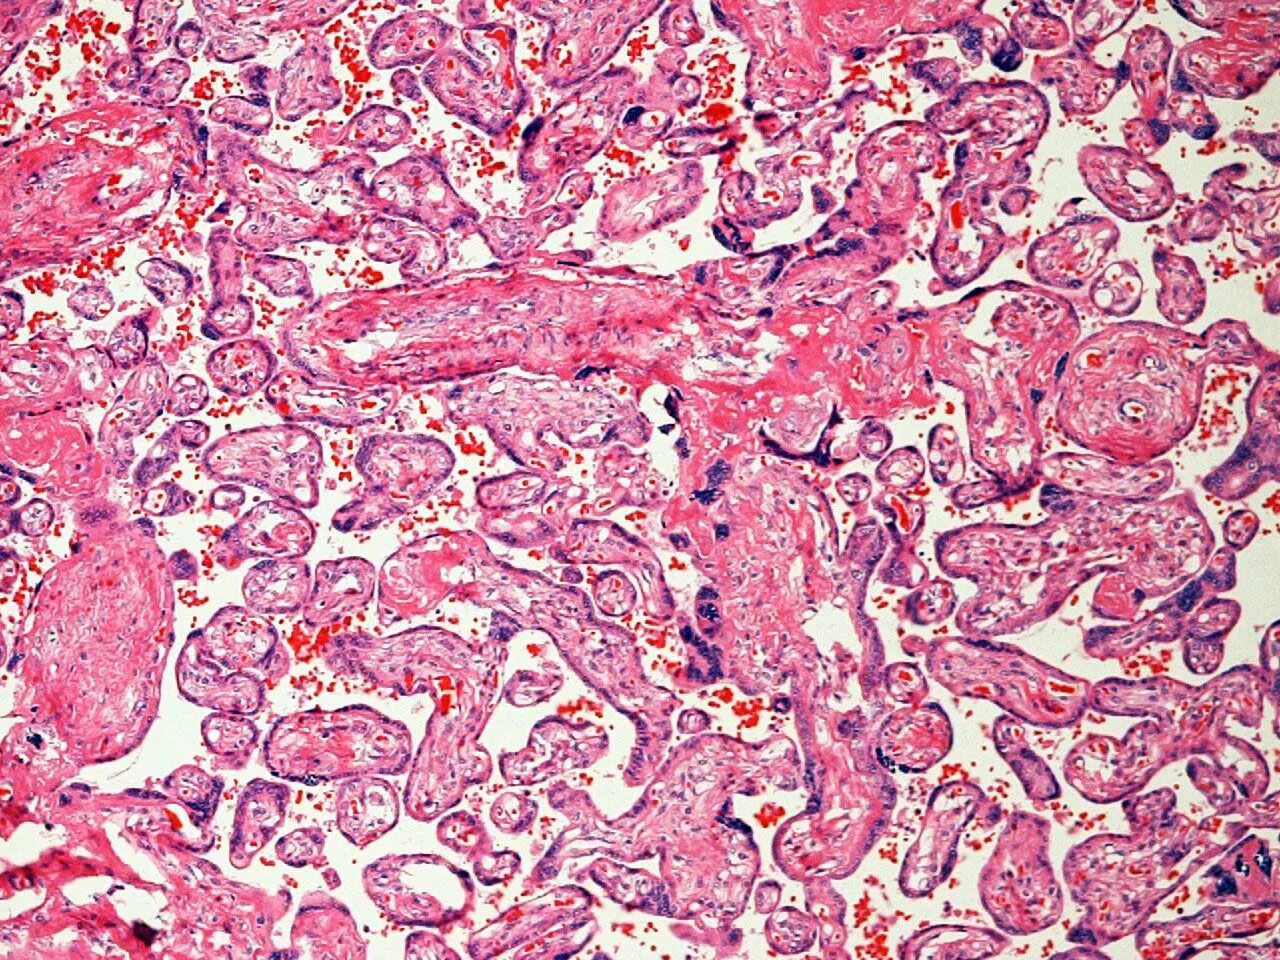

Беременность гистология